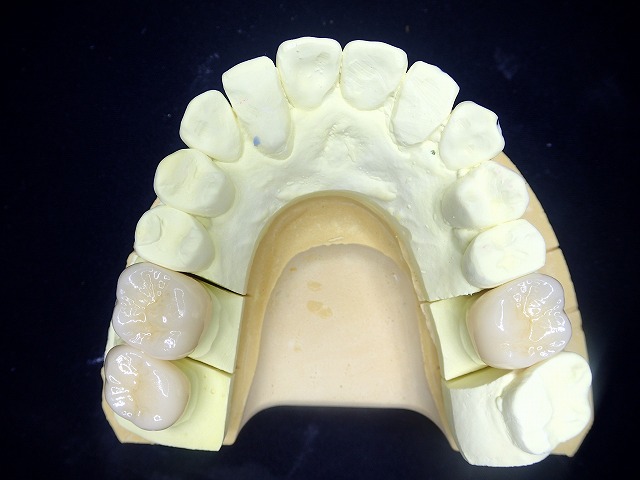

前歯の治療後 奥歯の銀歯を白くしたいとご希望

金属クラウンとジルコニアクラウンの比較

その後 銀歯も白くしたいとのご希望がありました

ジルコニアとの比較すると

両側の奥歯を銀歯からジルコニアに交換

通院期間が限られているので

期間内に可能な限り交換をしました。